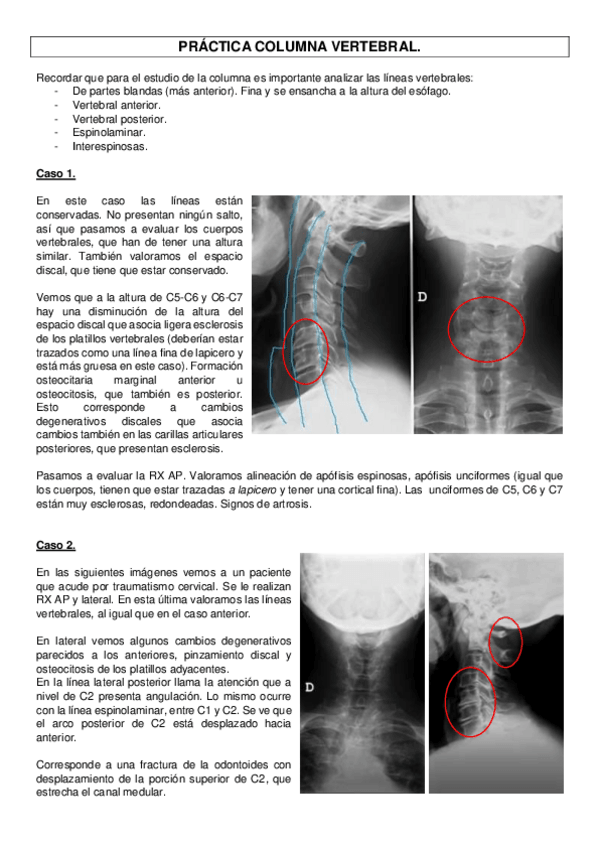

practicas-de-columna-vertebral.pdf

PRACTICA-COLUMNA-VERTEBRAL.pdf